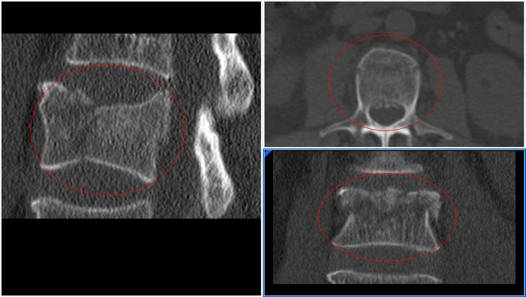

Complicaciones debidas a la osteoporosis.

La osteoporosis aumenta el riesgo de fractura en la vértebra que está por encima de los tornillos. Por otro lado los tornillos cogen peor y es más fácil que tengan holgura por lo que los pacientes con Párkinson tienen más riesgo de no fusión o pseudoartrosis.